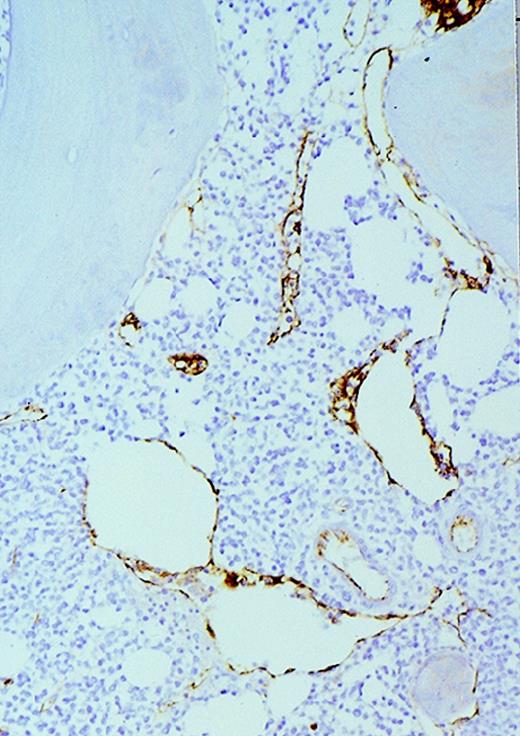

High-power view of vascularity of normal and AML marrow specimens.

Normal or AML bone marrow samples were stained for vWF expression (see Methods). A = 600× view of normal bone marrow showing positive staining in a megakaryocyte as well as 1 vessel. B = 400× view of representative AML marrow showing numerous vessels. Note that some of the vessels are large with irregular and bizarre shapes. C = 600× view of representative AML marrow showing details of vascular endothelial cell staining.